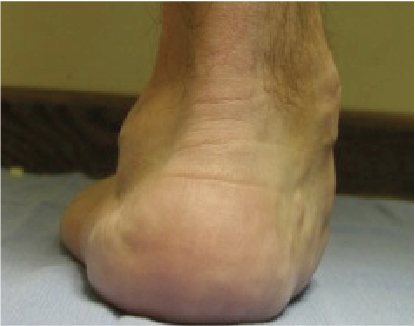

Patients with stage 2 PTTD present with a variety of deformities depending on planal dominance of the deformity. In patients with an unstable naviculocuneiform joint, one may note a sagittal plane collapse with a medial column sag demonstrating a naviculocuneiform fault radiographically. In transverse planal dominant deformities, one will see the too many toes sign with abduction of the midfoot and forefoot. The frontal plane deformities have a moderate heel valgus presentation with a forefoot supinatus or varus condition. The inability to perform a single limb rise test without inversion of the heel is common for advanced deformities where the function of the posterior tibial tendon has been lost due to an attenuated or ruptured posterior tibial tendon.

The performance of Jack’s test will help reveal the reducibility of the flatfoot deformity.6 A test I commonly perform on my patients involves external rotation of the leg with maintenance of lateral column weightbearing while I find the midtarsal joint neutral position. I have the patient hold his or her foot in this position, and evaluate the forefoot position. If I can manually reduce the deformity to weightbearing on the first ray, I consider this forefoot supinatus, which will reduce once I have addressed the proximal deformity by improving the lever of the peroneus longus tendon. If I cannot manually reduce the forefoot deformity, it is a forefoot varus that requires surgical correction with a Lapidus procedure, Cotton osteotomy, or wedging the naviculocuneiform arthrodesis. It is important to assess the difference between forefoot supinatus and forefoot varus.